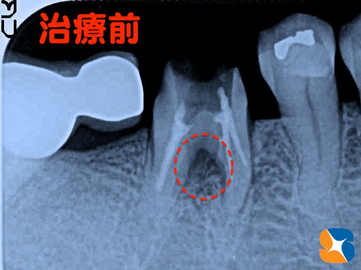

Dr:「レントゲンで確認しますね。歯が割れていたり、ヒビが入っていたりしていなければ、抜歯は不必要かもしれませんよ」

歯茎が膿んでいた所をレントゲンで確認 上記写真の膿んでいた所(=赤点)をレントゲンで確認すると、黒色の濃い影(=赤点)が写っていました。根と根の股間にトラブルが生じていることが判明しました。